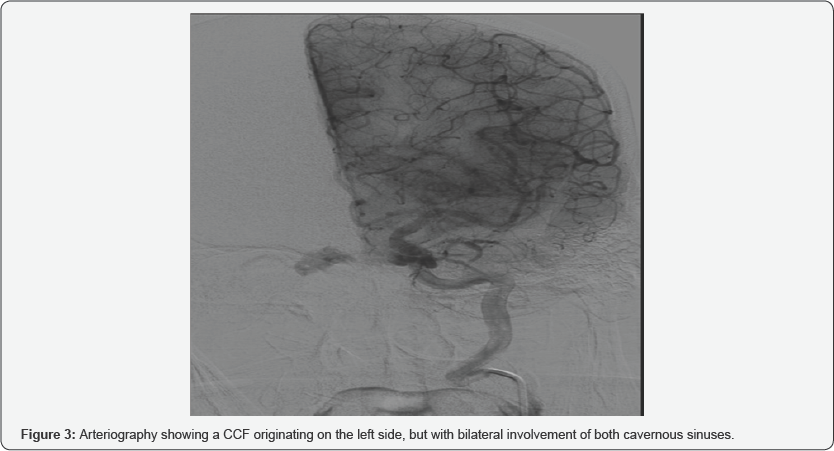

In a period of 1 year between March 2016 and May 2017, eight patients have been diagnosed and treated by CCF in our hospital. Of these eight patients, three were women and five men, with an average age of 52.9 years (range 25-77 years). All the patients in our series had exophthalmos, 62 % also associated diplopia and chemosis, and in 25 % they manifested headache or auscultate fro nto-orbital murmurs (Figure 1). In a patient with loss of visual acuity, a choroidal detachment was observed on MRI, a complication that can be associated with CCF (Figure 2). In 6 patients, the ocular symptoms were unilateral (75%): two patients with involvement of the right cavernous sinus and four patients with left involvement), being bilateral in the two remaining patients (Figure 3) [1-4].